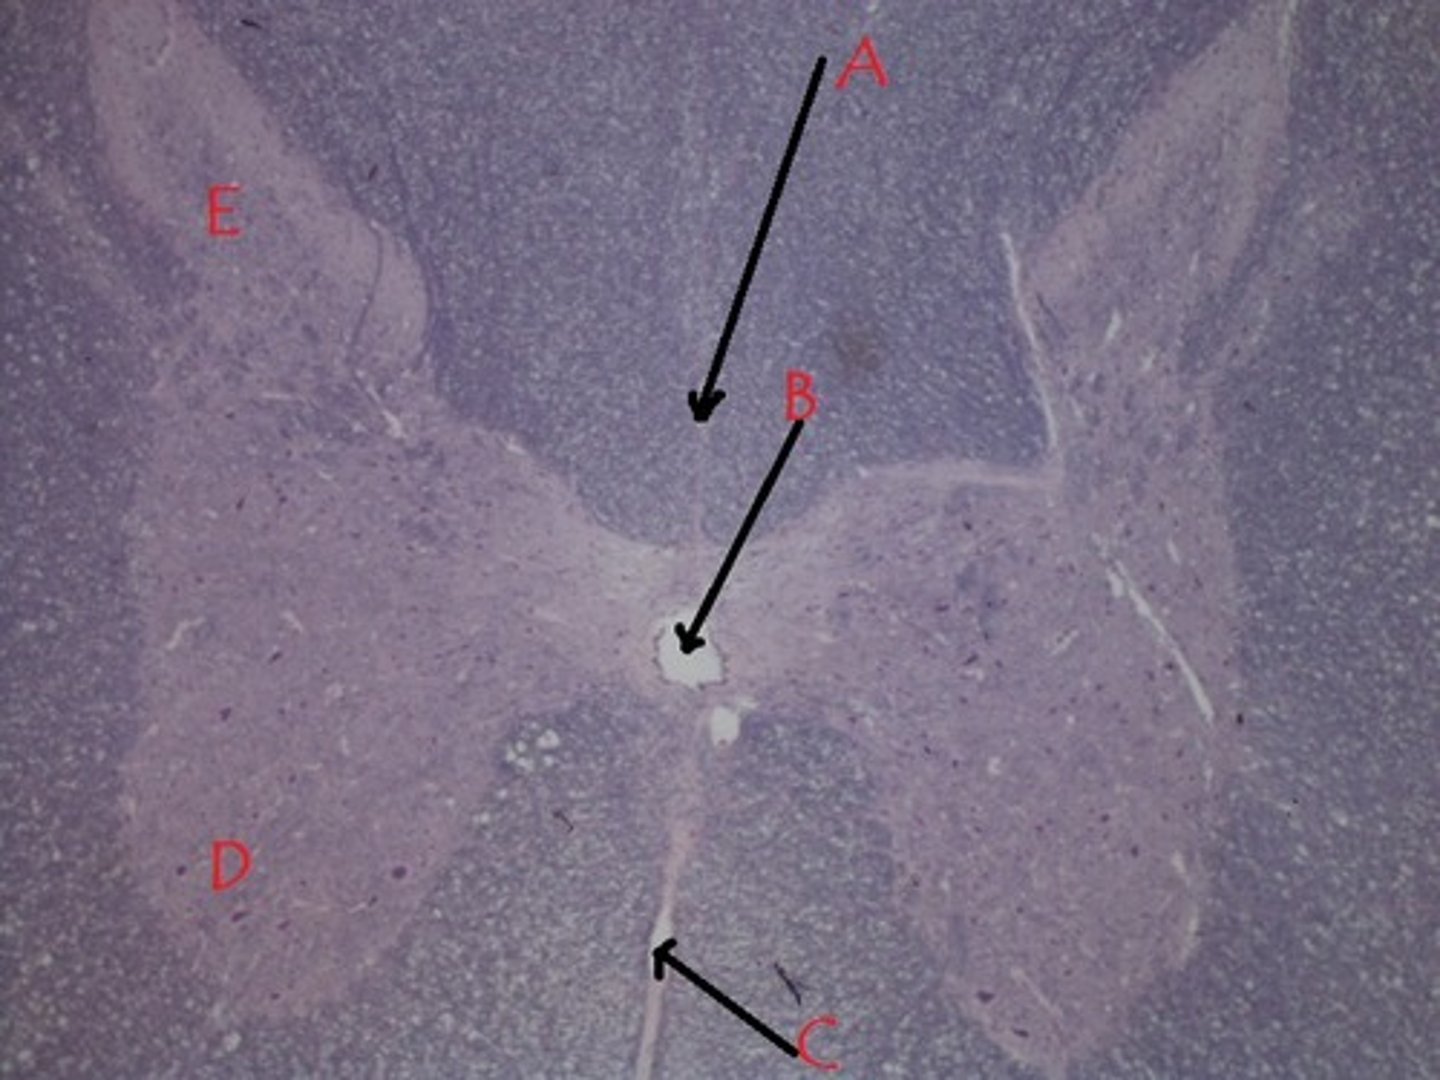

What is the area labelled A called?

subarachnoid space

What is the area labelled B called?

central canal

What is the area labelled C called?

posterior gray horn

Identify A

lateral gray horn

Identify B.

anterior gray horn

Identify C.

A

Which lettered area does not contain CSF?